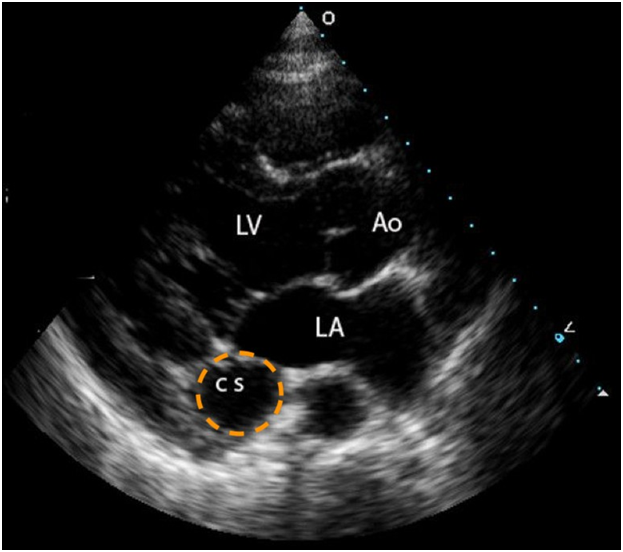

Figure 2 Echo cardiogram: parastern all on gax is view, observing dilated coronary sinus(CS), Aorta(AO), Left Atrium(LA), Left Ventricle(LV).

The diagnosis can be made by Echocardiogram: transthoracic (TTE) or transesophageal (TEE). TEE has an increased sensitivity and also facilitates the visualization of associated anomalies. On TTE A three vessel view on the echocardiogram will contribute to the diagnosis, going from left to right the vessels observed are the ductusarteriosus, aortic arch and RSVC, if the latter is absent then the LSVC will be seen on the left of the arterial duct. Confirmation is then made via long axis view showing the LSVC draining into a dilated coronary sinus.2,3 Confirmation can be achieved via CT, venography, or MRI.